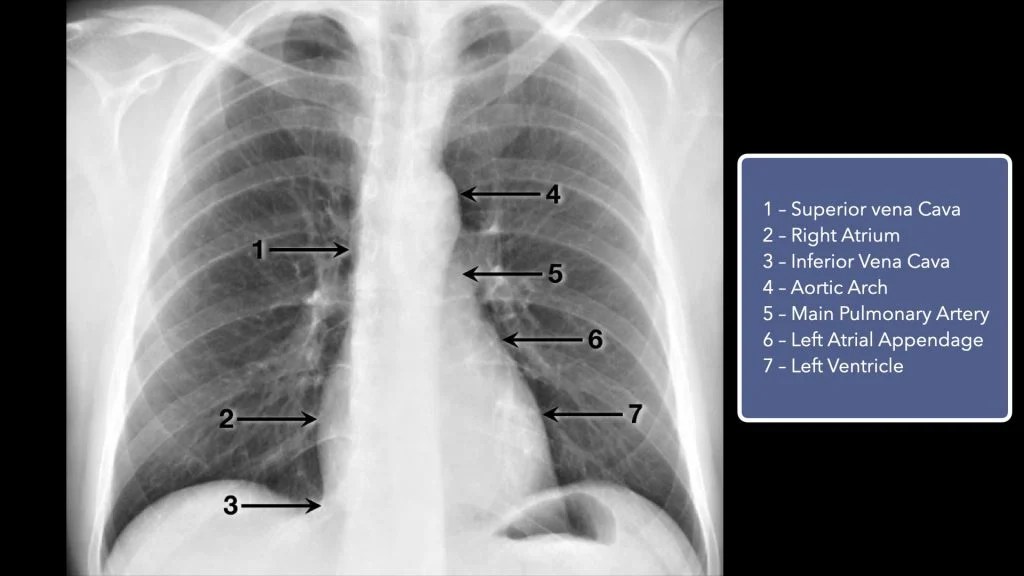

A normal PA chest Xray demonstrating the normal anatomy. Download Chest X Ray Markings An interstitial lung pattern is a regular descriptive term used when reporting a plain chest radiograph. On a cxr the most common pattern is reticular. In fact every radiologst should be an expert in chest film reading. Lines are usually less than 1 mm in width and are. Chest X Ray Markings.

Normal, Labelled, Chest xray, with Cardiovascular Structures Chest X Ray Markings An interstitial lung pattern is a regular descriptive term used when reporting a plain chest radiograph. On a cxr the most common pattern is reticular. Lines are usually less than 1 mm in width and are. In fact every radiologst should be an expert in chest film reading. Chest X Ray Markings.